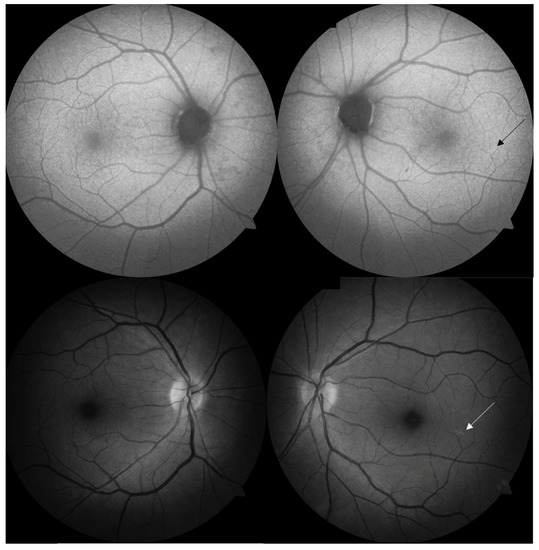

The intraocular pressure (ICARE-tonometr) was within the normal range (20.6 mmHg in both eyes). No abnormalities appeared on the optical coherent tomography (OCT) of the optic nerve, the ganglion cell complex (GCL + IPL) or the static perimetry. The macular OCT test did, however, show thickening of the central part of the macula (Figure 2), but macular angio-OCT and visual evoked potential (VEP) tests showed no anomalies. Indirect ophthalmoscopy revealed the constriction of retinal arteries, arterial wall thickening and arteriovenous nicking (Figure 3A). In addition, there were other interesting findings, namely peripheral RPE atrophy and focal hyperfluorescence in the temporal macula region at the inferior vascular temporal arch (Figure 3B,C), which was thereafter confirmed in the fluorescein angiography (FA) (Figure 4) and OCT of the left eye.

Eye fundus fluorescein angiography of the patient with CADASIL. (A) Constricted retinal arteries in both eyes. (B) Retinal pigment epithelium (RPE) atrophy in both eyes, but mainly in the left eye. (C) Retinal pigment epithelium (RPE) atrophy with focal drusen in the left eye.

Figure 4.

Fluorescein angiography of the right and the left eye. Discrete retinal lesions in the left eye (the arrow demonstrates focal drusen).

The retinal drusen were observed in the retina of the left eye (Figure 5).